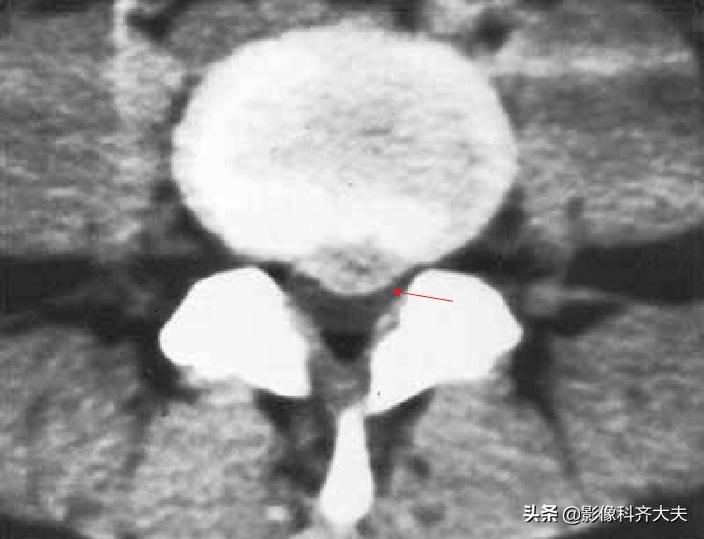

Schmorl结节(许莫氏结节)

Schmorl结节(许莫氏结节),是椎间盘退变时,软骨板变薄及玻璃样变,甚至消失。髓核经软骨板的薄弱或者缺损部疝入椎体内,在椎体内形成软骨结节。

是髓核于椎体上面或者下面形成的圆形或者半圆形的骨质凹陷区,其边缘有硬化。可对称见于相邻两个椎体的上下面,并且可以累及多个椎体。

可以说算是一种特殊类型的椎间盘突出。只不过不像普通椎间盘突出是突出于椎体后缘,而是突出到上下椎体里!

在影像上看,椎体上下缘弧形的凹陷或者骨性透亮区,伴有不同程度的边缘硬化,广泛硬化时椎体呈象牙质样。

Schmorl结节(许莫氏结节)示意图

许莫氏结节并骶管内囊肿